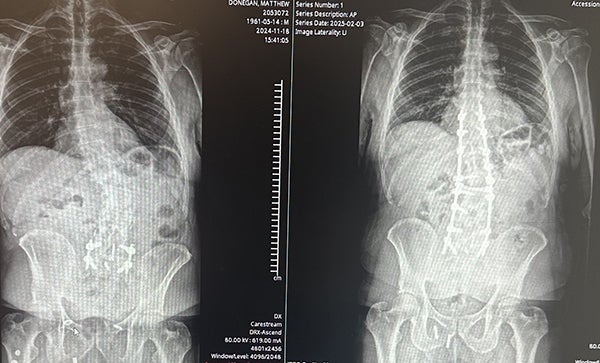

In adulthood, what was initially diagnosed as an eight-degree curve, became a 15-degree curve, then a 30-degree curve and eventually a 41-degree curve, rendering everyday activities virtually impossible.

Matt met Dr. Deol in January 2024. After clinically evaluating Matt and reviewing his X-rays and magnetic resonance imaging (MRI), Dr. Deol discussed that it was imperative to exhaust non-operative treatment options. Subsequently, Matt tried acupuncture, physical therapy, epidural steroid injections and pain management. Given his ongoing severe back and leg pain and significant disability despite extensive non-operative treatment, Dr. Deol advised Matt that he would likely benefit from spinal decompression and reconstructive surgery.

With numerous options tried and failed, Dr. Deol scheduled Matt for surgery at WakeMed Cary Hospital on January 15, 2025. The six-hour surgery was completed successfully, decompressing the spinal canal and correcting his deformity.

"Matt had undergone three prior spinal surgeries and unfortunately had developed severe spinal stenosis and spinal deformity above his prior fusion surgery. This caused him to have significant disability and pain. He failed extensive non-operative treatment and stated that he could no longer live with this kind of pain and was willing to take the risk of further spinal surgery.

"The surgery involved decompressing his spinal canal above the prior fusion, correcting the deformity and reconstructing the spine above his old fusion. The goal of the surgery was to allow him to return to a relatively pain-free life, walking upright and enjoying his prior activities. He' has been a great patient and very appreciative."

"Thanks to Dr. Deol, none of the negatives came out of my surgery. Before surgery, I couldn't leave the house. There were days I couldn't walk. I would get out of bed in the morning screaming because my rib was pressing down on my hip bone due to the extreme curve. Since this surgery, I regained three inches lost to deformity. I can mow the lawn again. I can exercise and lift weights. I can tie my shoes. I occasionally take over-the-counter pain medication. I still have some muscle and scar tissue that is breaking up, but the truth is Dr. Deol gave me a brand-new life."